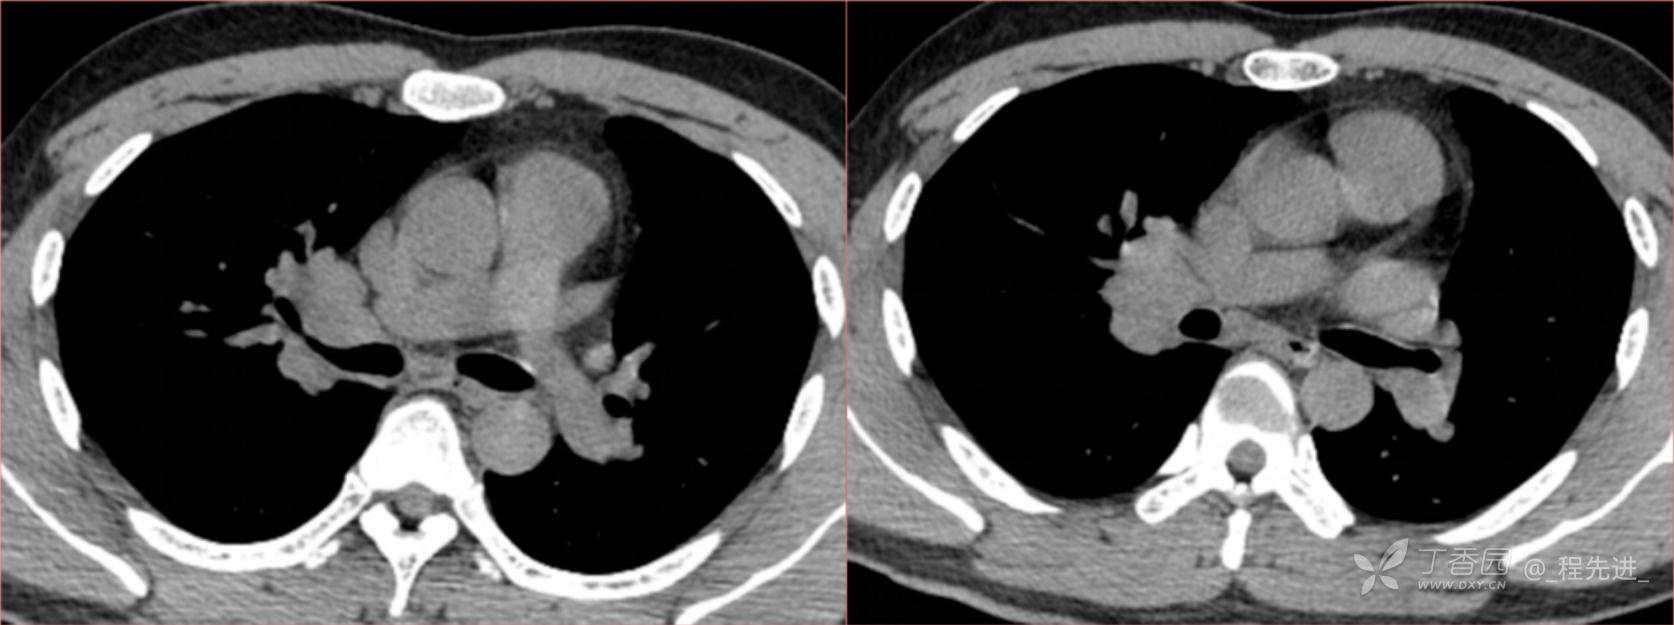

1月特别精彩病例|阵发性刺激性咳嗽,咳少量白色粘液痰1周,期待你的挑战【结果公布】

患者年龄:34岁

简要病史:患者一周前无明显诱因出现阵发性刺激性咳嗽,咳少量白色粘液痰,咳嗽无明显昼夜节律性,无发热、畏冷、寒战,无头痛、胸闷、胸痛,自行服药后 (具体不详) 症状无缓解,3天前当地医院胸片检查示右上病变

辅助检查:肺肿瘤标志物: 神经元特异性烯醇化酶(NSE): 35.72ng/ml(参考值0-16.3);非小细胞肺癌相关抗原211、癌胚抗原、糖类抗原125、铁蛋白、鳞状细胞癌抗原未见异常